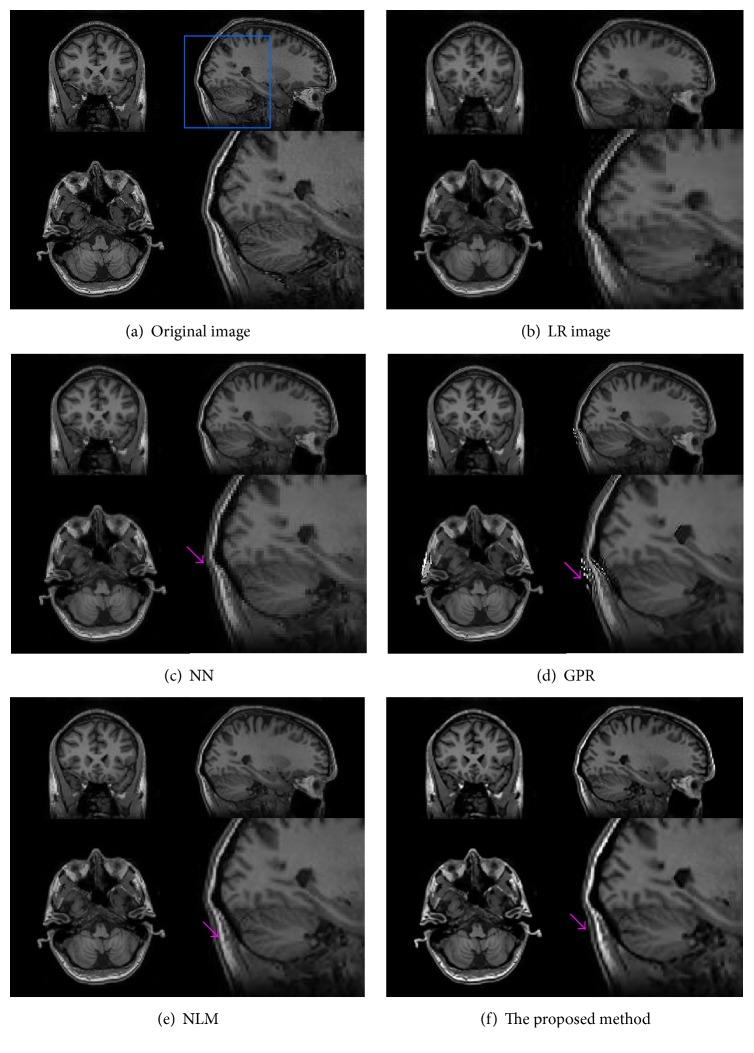

The spatial resolution of magnetic resonance imaging (MRI) is often limited due to several reasons, including a short data acquisition time. Several advanced interpolation-based image upsampling algorithms have been developed to increase the resolution of MR images. These methods estimate the voxel intensity in a high-resolution (HR) image by a weighted combination of voxels in the original low-resolution (LR) MR image. As these methods fall into the zero-order point estimation framework, they only include a local constant approximation of the image voxel and hence cannot fully represent the underlying image structure(s). To this end, we extend the existing zero-order point estimation to higher orders of regression, allowing us to approximate a mapping function between local LR-HR image patches by a polynomial function. Extensive experiments on open-access MR image datasets and actual clinical MR images demonstrate that our algorithm can maintain sharp edges and preserve fine details, while the current state-of-the-art algorithms remain prone to some visual artifacts such as blurring and staircasing artifacts.

由于多种原因,包括数据采集时间短,磁共振成像(MRI)的空间分辨率常常受到限制。已经开发了几种基于先进插值的图像超分辨率算法来提高MR图像的分辨率。这些方法通过原始低分辨率(LR)MR图像中体素的加权组合来估计高分辨率(HR)图像中的体素强度。由于这些方法属于零阶点估计框架,它们仅包括图像体素的局部常数近似,因此不能完全表示潜在的图像结构。为此,我们将现有的零阶点估计扩展到更高阶的回归,使我们能够通过多项式函数近似局部LR-HR图像块之间的映射函数。在开放获取的MR图像数据集和实际临床MR图像上进行的大量实验表明,我们的算法可以保持清晰的边缘并保留精细的细节,而当前的最先进算法仍然容易出现一些视觉伪影,如模糊和阶梯状伪影。